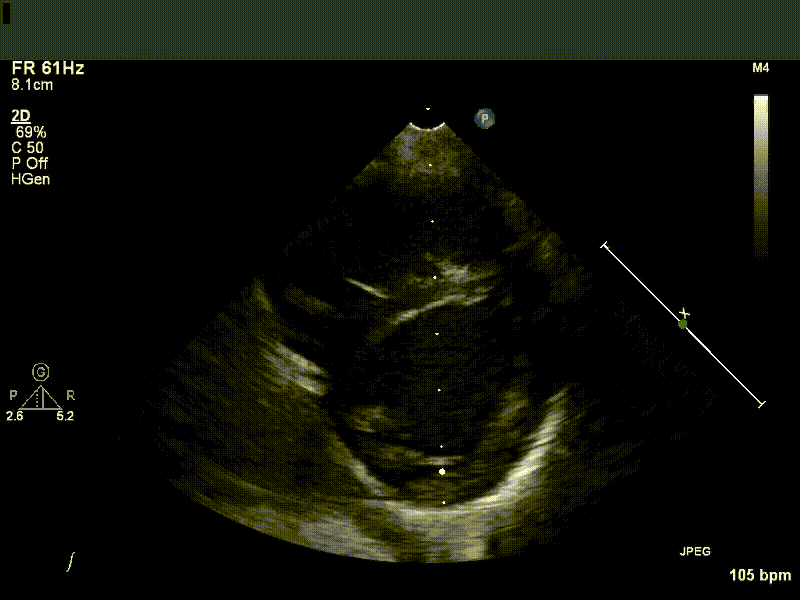

Echocardiography is integral to all aspects of patient care in Cardiology. Over the course of your 6 rotations in the Echo Lab, you will go from a novice to a highly sophisticated clinical user of this imaging modality.

To most effectively use echocardiography, you need a strong foundation in the physics that make the images possible. The modules that follow are designed to present this foundation in a way that is accessible and clinically relevant, and to help you reflect and synthesize the concepts as you go.